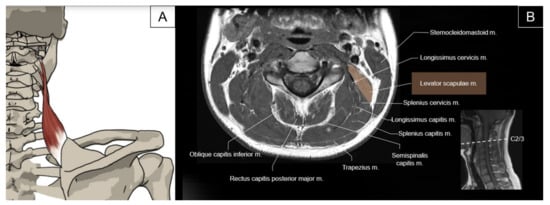

4.1. Splenius Capitis and Longissimus Capitis

4.1.1. Anatomy

4.1.2. Sonographic Scanning

4.1.3. Clinical Relevance